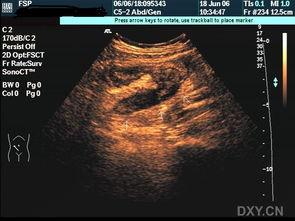

阑尾炎,这个名字听起来就让人心生恐惧。那么,阑尾炎的照片又会是什么样子呢?首先,我们要知道,阑尾炎是一种炎症性疾病,通常发生在人体的阑尾部位。阑尾,这个看似不起眼的小器官,位于人体右下腹,连接着盲肠。

当阑尾发炎时,它的外观会发生一些变化。通过一些医学图片,我们可以看到,阑尾炎的阑尾会变得红肿、增大,甚至可能形成脓肿。这些照片,虽然有些令人不适,但却是医生诊断阑尾炎的重要依据。

那么,阑尾炎的照片中,我们能否看到这些成因的痕迹呢?答案是可以的。在医学照片中,我们可以看到,阑尾炎的阑尾壁会变得增厚,甚至出现脓肿。这些变化,都是细菌感染和炎症反应的结果。